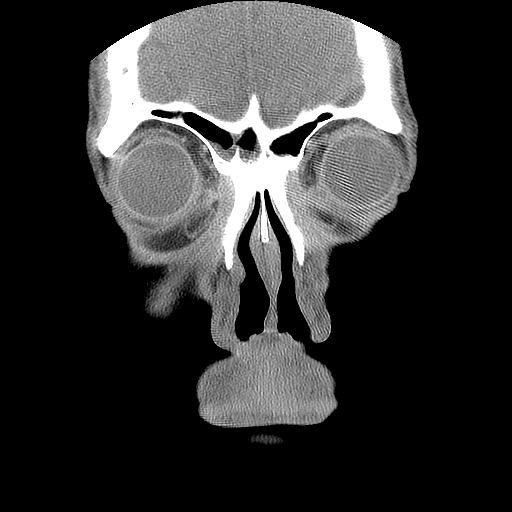

男,38岁,鼻塞、头痛2个月,要求鼻窦ct检查。

右侧上颌窦、蝶窦、筛窦、额窦及左侧上颌窦慢性炎症。

右侧鼻中隔左偏,右侧上颌窦、筛窦、额窦慢性炎性病变。右侧上颌窦开口粘膜增厚。

1)副鼻窦炎。2)右侧中鼻道及总鼻道粘膜息肉样变。3)双侧中下鼻甲肥大。4)鼻中隔轻度左突偏曲。